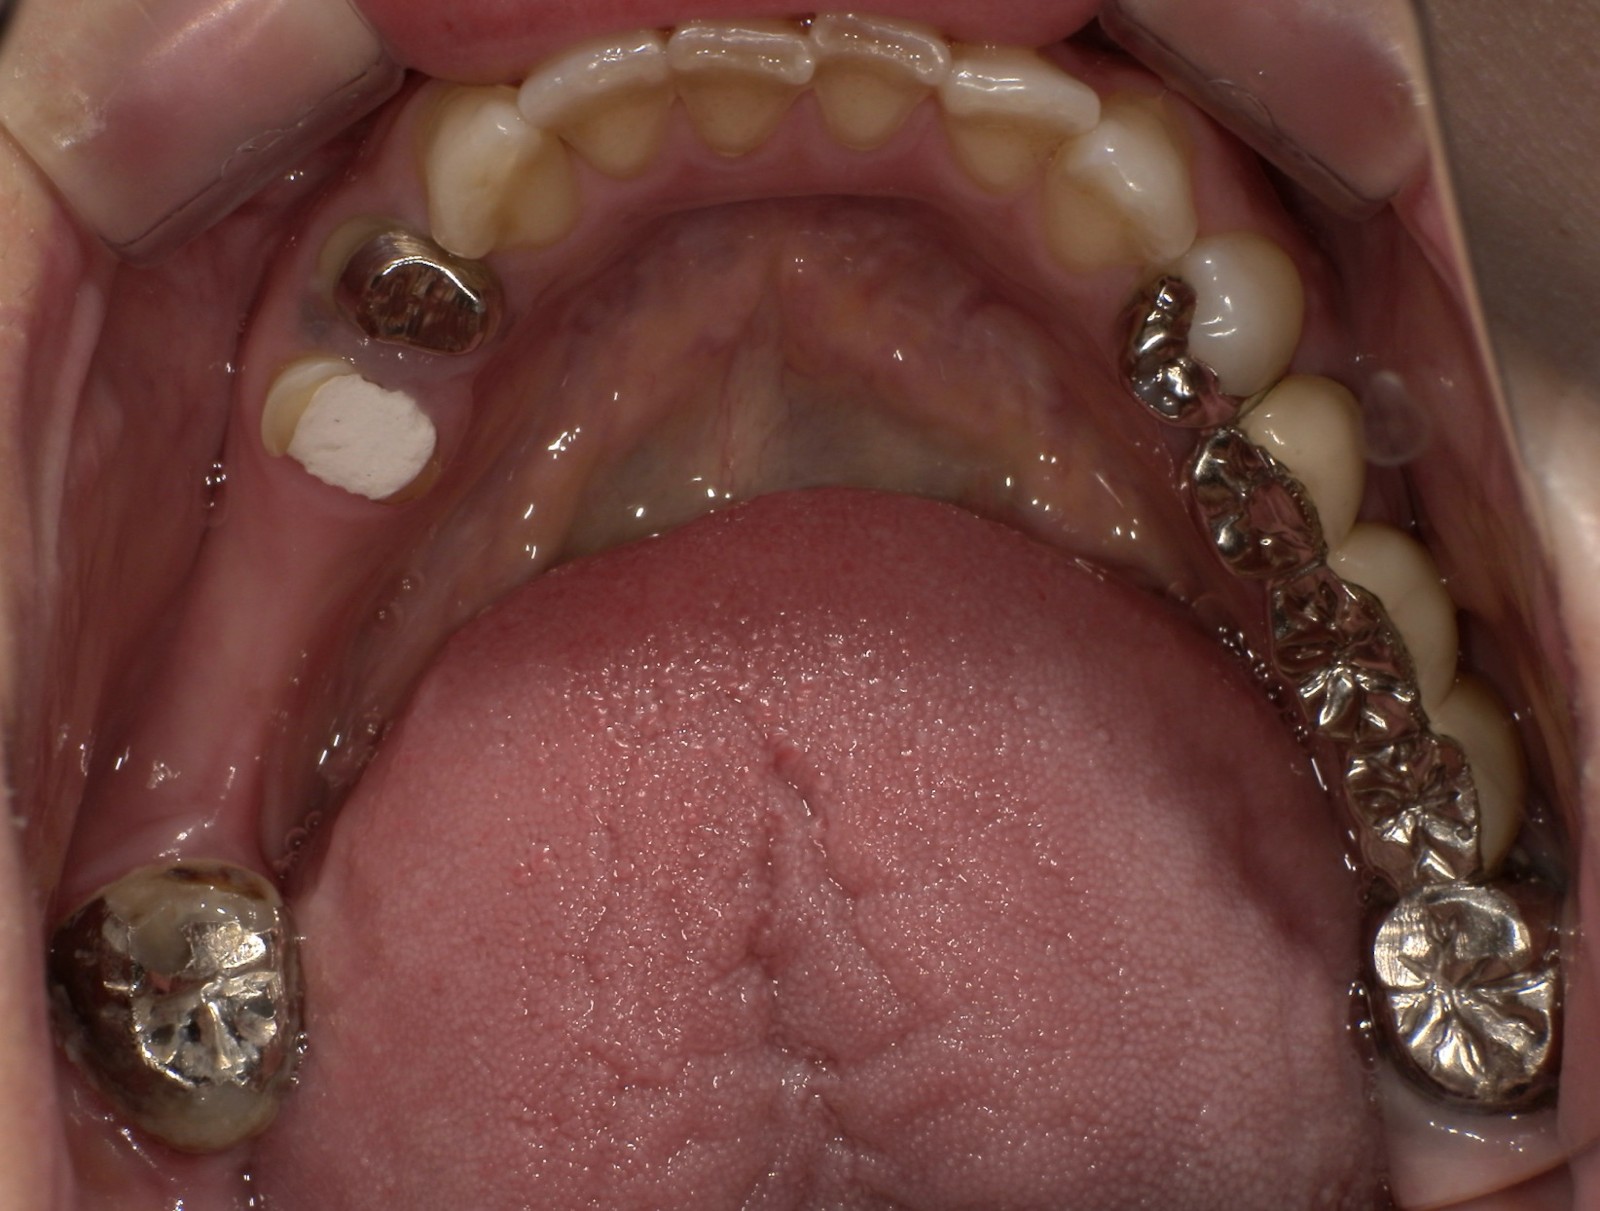

CASE 02

Before

After

施術内容下の銀歯を白くしたいとのこと。下顎左右第一大臼歯の銀歯をジルコニアクラウンに交換。

治療期間2か月

リスク・副作用ジルコニアは非常に強度が高いですが、強い衝撃や極端に強い噛み合わせ、歯ぎしり・食いしばりなどがある場合、まれに割れたり欠けたりする可能性があります。

費用198,000円

※表示金額は全て税込みです。